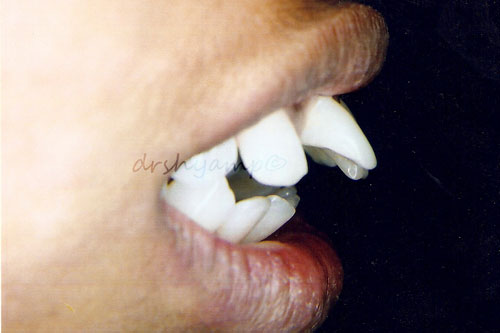

anterior deep bite

-

anterior deep bite

-

anterior deep bite

-

anterior deep bite

-

anterior deep bite

-

anterior deep bite

Correction of anterior deep bite